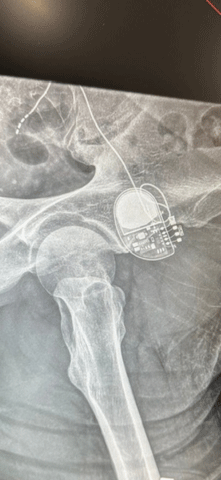

The SNS device is implanted under the skin at the top of the buttocks, where it delivers electrical pulses to stimulate the sacral nerve. Marco B. Zoccali, MD, colorectal surgeon and principal investigator, explains, "By stimulating a sacral nerve root, we can actually trigger the parasympathetic nerves to release impulses that restore balance in the inflammatory versus anti-inflammatory signals in the intestine."